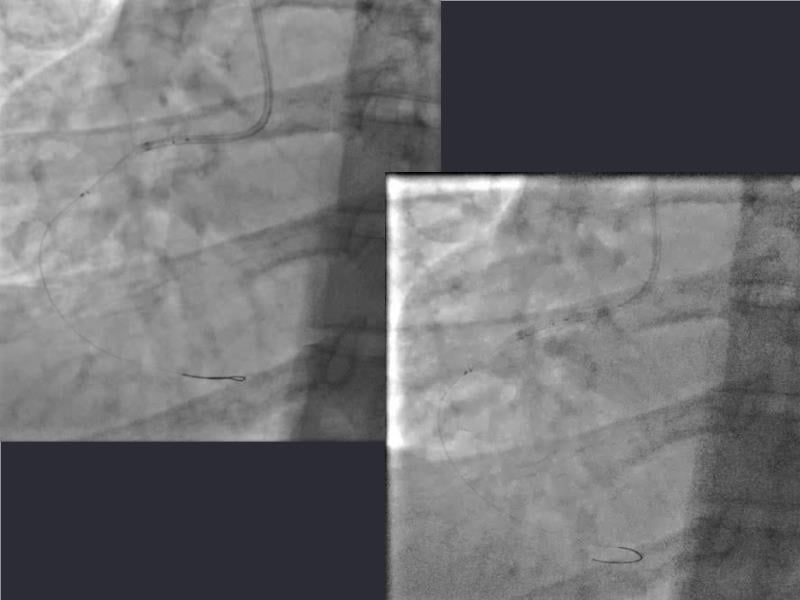

This session is a valuable resource for grasping innovative strategies in handling bifurcation and extended diffuse lesions through dedicated stenting solutions. Explore insights into the advanced Myval next-generation THV technology, unveiling its distinctive features, procedural advantages, and clinical outcomes across a diverse patient pool. Gain understanding into the CorAlign technique, ensuring accurate commissural and coronary alignment while maintaining coronary access. Additionally, delve into the techniques for precise sizing, positioning, and deploying of Myval THV.

- To understand novel tools and techniques for effective management of bifurcation lesions and long diffused lesions using dedicated stenting solutions